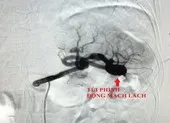

Tại đây, sau khi thăm khám và chẩn đoán bằng hình ảnh, các bác sĩ (BS) nhận định ông M. mắc khối u phì đại lan rộng từ vùng trán xuyên qua cơ nâng mi mắt trên và vào trong niêm mạc. Khối u xâm lấn, chảy xệ vùi lấp mắt phải khiến ông M. suốt 10 năm qua không thấy ánh sáng. Do vậy, các BS quyết định phẫu thuật để khối u không tiếp tục tăng sinh, xơ cứng mạch máu, gây mù lòa vĩnh viễn.

Điều đáng lưu ý, do mạch máu to và mô xơ cứng nên các BS hết sức thận trọng trong quá trình phẫu thuật cắt bỏ. Bỡi chỉ một sơ suất nhỏ có thể dẫn đến hoại tử toàn bộ vùng mắt phải

Theo TS-BS Tú Dung, mẫu bệnh phẩm được cắt rời từ khối u mạch máu vùng mắt của ông M. sẽ được BV gửi tới các phòng xét nghiệm trong và ngoài nước để phân tích. Mục đích để tìm ra nguyên nhân và hướng điều trị khắc phục triệt để khối u trên khuôn mặt của ông M. trong thời gian tới.